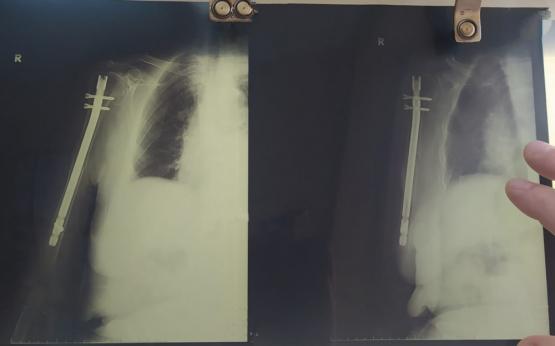

В  БСМП Ростове провели высокотехнологичную операцию 94-летней пациентке со сложным переломом плеча. Об этом сообщили в пресс-службе регионального министерства здравоохранения.

Серьезную травму пожилая женщина получила у себя дома. Она оступилась и упала прямо возле кровати, ее рука попала в конструкцию батареи, находившейся рядом. В результате – сложный перелом плеча со смещением. Когда выяснилось, что требуется операция, родственники пенсионерки очень волновались. Беспокоились, как она ее перенесет в столь почетном возрасте.

В начале лечения была применена региональная анестезия: у пациентки «отключили» только руку, на которой предстояло выполнить операцию. Сама она находилась в сознании. Затем была проведена операция по малоинвазивной технологии.

Это хирургический метод восстановления длинных трубчатых костей: через небольшие кожные разрезы в поврежденное место вводится специальный штифт, фиксирующий костные отломки. Зона перелома в процессе операции не открывается, что позволяет сохранить кровоснабжение и обеспечивает возможность быстрого сращивания перелома.

- Очень важно, что после проведения такой операции пациенту не требуется гипс и какие-либо сковывающие повязки. Что немаловажно для возрастных людей. Человек выписывается на пятый день после поступления. И далее наблюдается амбулаторно по месту жительства,  - рассказал врач травматолог-ортопед отделения травматологии № 1 ГБСМП Ростова-на-Дону Олег Литвиненко.

Сейчас 94-летняя женщина уже выписана из больницы. Врачи оценивают ее состояние  как удовлетворительное.